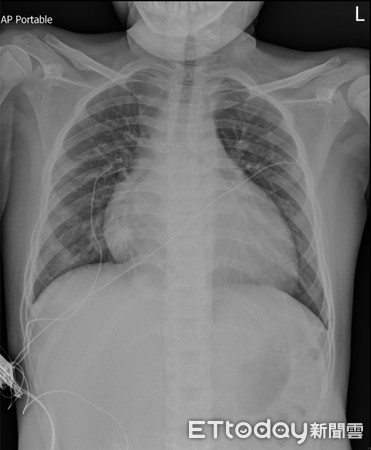

Ảnh chụp X-quang của Tiểu Lâm